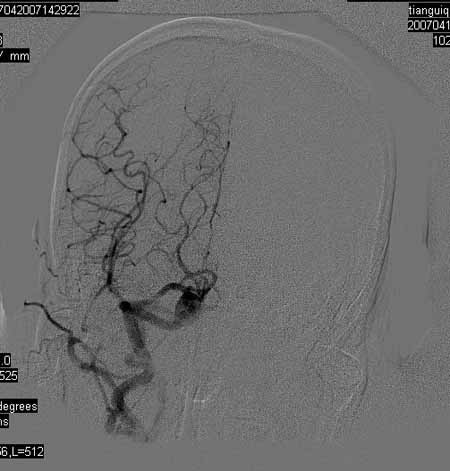

标题: DSA0093:脑血管造影

女,63岁,左侧额、枕叶脑梗塞。

右肾动脉及左颈内动脉起始部狭窄(考虑动脉硬化引起的),大脑中动脉分支减少.